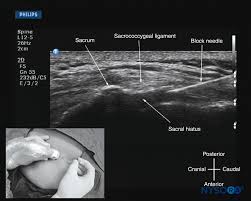

وبالإمكان خفض هذه الاحتمالية عندما يتم اختيار #المريض المناسب طبيا لهذا الإجراء وعندما يتم إجراء #التخدير_النصفي من قبل #طبيب_تخدير استشاري متمرس لديه المعرفة والقدرة على التعامل مع الحالات واستخدام الأشعة السينية او فوق الصوتية للحالات الصعبة

3️⃣اصابة العصب الدائم (متلازمة ذيل الفرس) Conus medullaris syndrome

وهو عبارة عن اصابة غير مكتملة للحبل الشوكي ولا تسبب #الشلل_النصفي وقد بينت دراسة فرنسية ان نسبة الإصابة بهذه المضاعفة تعتبر ضئيلة للغاية وهي ١ في كل ١٧٨٦٦٠ حالة مع العلم ان ٥٠٪ من الحالات كانت حالات #الولادة

٤.تضيق قناة الحبل الشوكي

٥.تزداد عند الاحساس بالكهرباء أثناء ادخال #الابرة